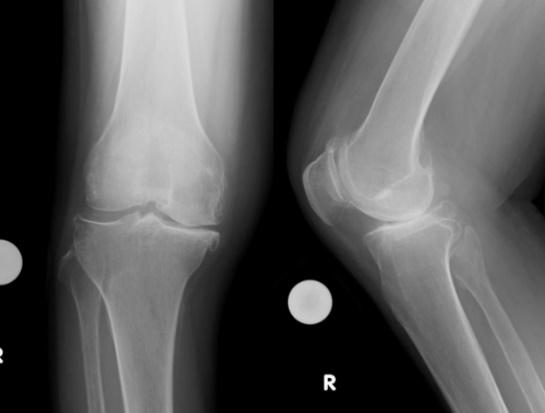

(2) 膝関節障害の代表的なものには、若年者における軟骨病変や、中高齢に発症する変形性膝関節症、膝骨壊死が挙げられます。

患者さんの年齢や活動性、日常生活の障害程度に合わせて患者さんに合ったオーダーメイドの治療法を心がけています。

前医での治療効果が認められなかった場合や、病期の進行した症例に対しては手術を行いますが、基本的にはまず保存的治療を行います。

治療法としては、減量や大腿四頭筋(太ももの表の筋肉)の筋力強化などのリハビリテーション、消炎鎮痛剤の内服・外用やヒアルロン酸の関節注射、サポーターや足底板などがあります。これらの保存的治療で症状が改善しない方には手術を行います。

変形性膝関節症や大腿骨内顆骨壊死症などに適応があります。

脛骨の近位部を骨切りし、O脚に変形した下肢を軽度X脚に矯正し、荷重による負担を膝外側に移動することによって、膝内側の痛みを緩和する方法です。変形の程度によって開大式と閉鎖式骨切り術を使い分けております。